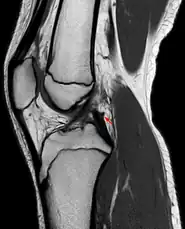

Posterior meniscofemoral ligament on MRI, coronal

Posterior meniscofemoral ligament (Wrisberg) behind the posterior horn of the lateral meniscus close to its insertion. Sometimes wrongly interpreted as a meniscal tear.